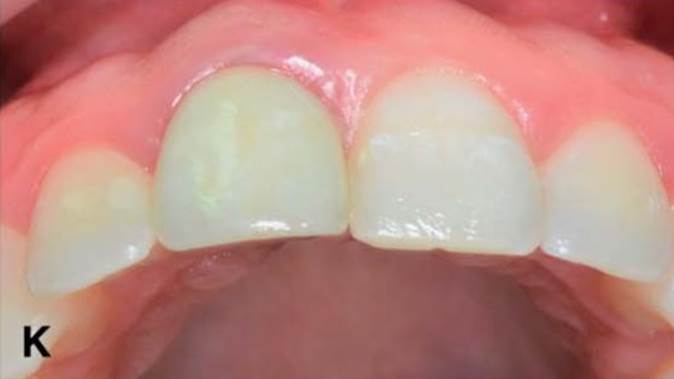

Clinical case: Immediate post-extraction insertion of implant & immediate loading

- Courtesy of Prof. Giuseppe Luongo, Italy -

Keywords

AnyRidge, immediate loading, single implant, multicenter study, maxillary anterior, Prof. Giuseppe Luongo, single replacement

Products:

AnyRidge implant system

Reference

Immediate functional loading of single implants: a multicenter study with 4 years of follow-up

/J Dent Res Dent Clin Dent Prospect 2018; 12(1):26-37 | doi: 10.15171/joddd.2018.005

https://www.ncbi.nlm.nih.gov/pubmed/29732018